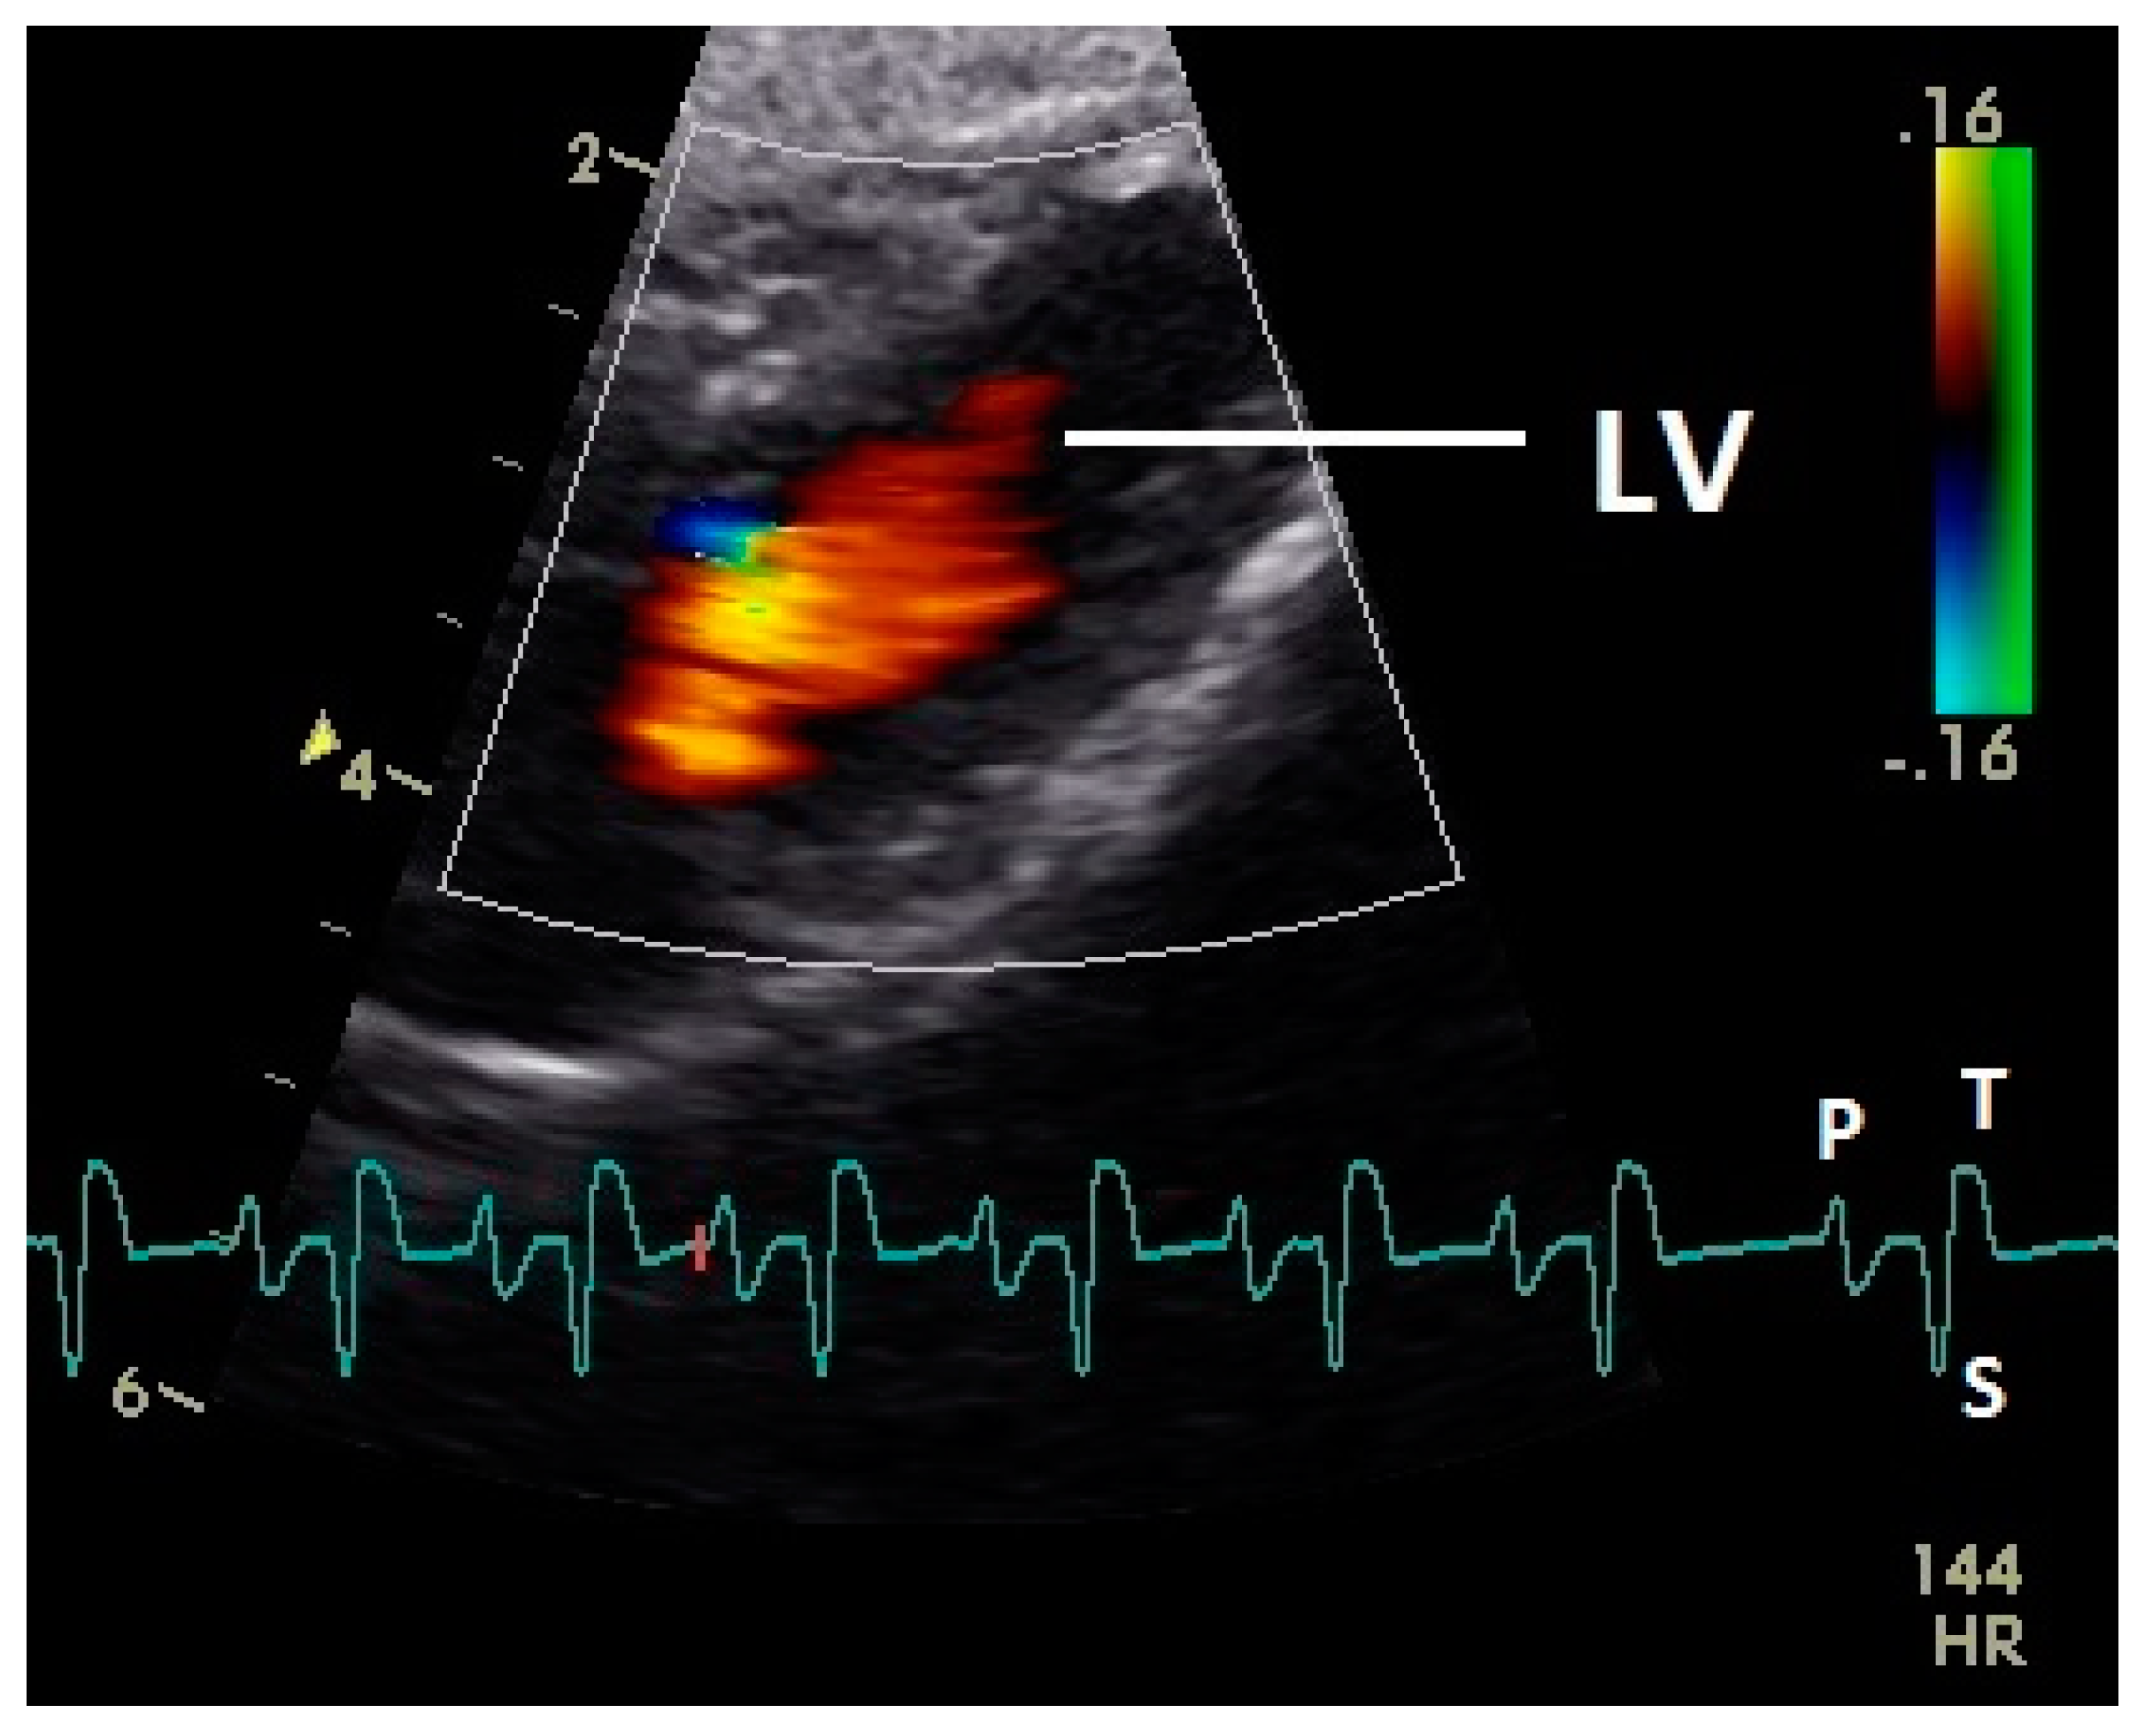

What Is a Color Doppler Test?

A Color Doppler ultrasound is a specialized imaging test that evaluates blood flow through arteries and veins. By using sound waves and color mapping, it helps doctors detect blockages, narrowing of blood vessels, clots, and abnormal blood circulation.